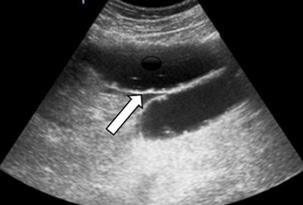

Issuu converts static files into: digital portfolios, online yearbooks, online catalogs, digital photo albums and more. Sign up and create your flipbook.